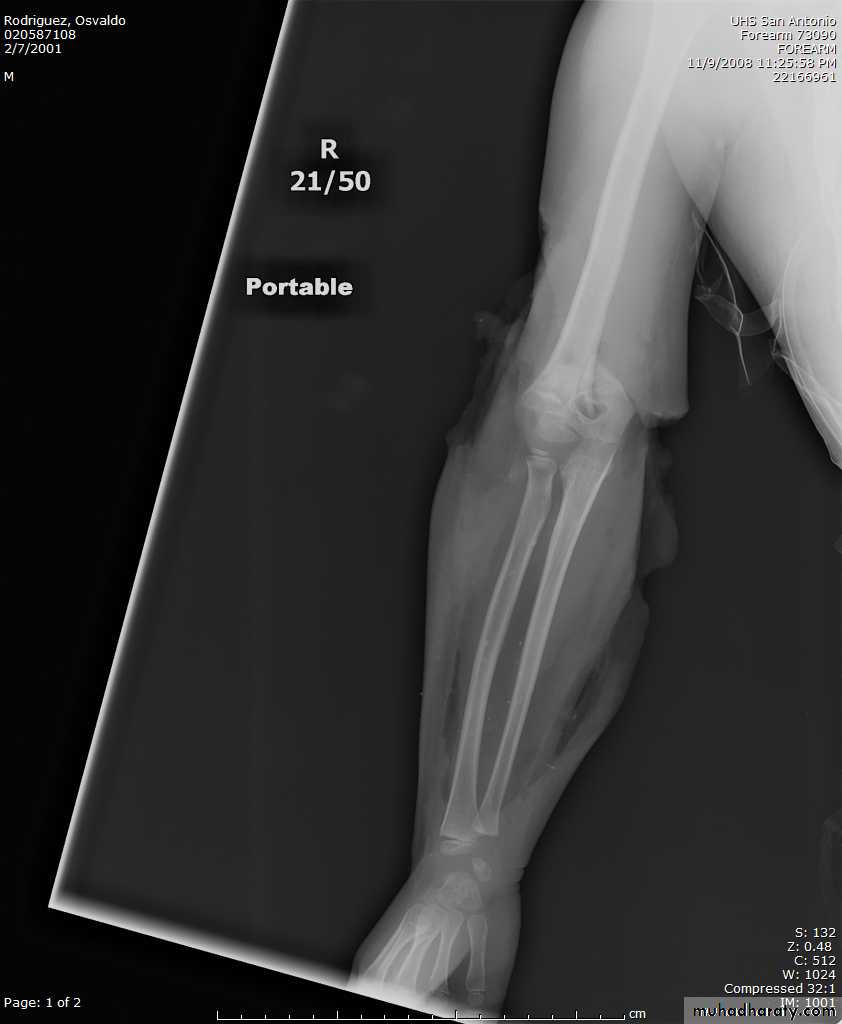

8 y.o. rolled over on an ATV

with mild closed head injuryClinical appearance

Only N-V deficit:

Anterior interosseous n. function weak

Radial A.

FCR Musc.Imaging Studies

How are we going to stabilize this boy’s fracture?